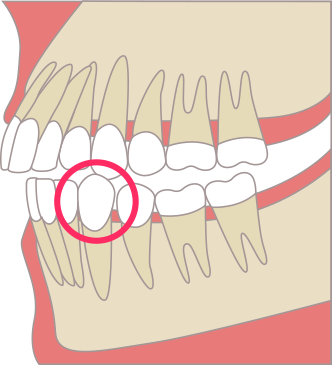

八重歯:犬歯が外に出ている場合

犬歯という歯が唇側に大きく出ていると、犬歯がかみ合いません。

歯は種類ごとに、機能があるため、犬歯がかみ合っていないということは、犬歯が機能していないということになります。

犬歯は、前歯と奥歯と違った大事な機能があります。犬歯は顎を横にスライドするときに機能します。ご飯を食べるとき、人は厳密にはカチカチ噛んでいるわけでなく、顎をスライドして咀嚼します。そのため、咀嚼する時には、横にずれる動きが存在しています。

犬歯が噛んでいないと、横の動きを他の歯で代償することになります。主に横の動きを代償する歯は、臼歯になります。臼歯は頑丈そうに見えて横の力に弱く、犬歯が噛んでいないと、経年的に奥歯が悪くなります。

奥歯を横の力から守るために、犬歯を矯正治療で移動させ、しっかりと機能させてあげることが必要です。

八重歯と(叢生)と奥歯への負担

正常な咬み合わせ(犬歯誘導)

犬歯がガイドし、奥歯が離れる

八重歯の場合(奥歯の干渉)

犬歯が機能せず、

奥歯が強く当たる(過度な負担)

破折・歯周病の

リスク